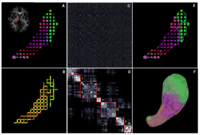

Improving fMRI Analysis using Supervised and Unsupervised LearningOne of the major goals in the analysis of fMRI data is the detection of networks in the brain with similar functional behavior. A wide variety of methods including hypothesis-driven statistical tests, supervised, and unsupervised learning methods have been employed to find these networks. In this project, we develop novel learning algorithms that enable more efficient inferences from fMRI measurements. More... New: G. Langs, Y. Tie, L. Rigolo, A.J. Golby, and P. Golland. Functional Geometry Alignment for Localization of Brain Areas. To appear in Proc. NIPS: Neural Information Processing Systems, 2010. New: A. Venkataraman, Y. Rathi, M. Kubicki, C-F. Westin and P. Golland. Joint Generative Model for fMRI/DWI and its Application to Population Studies. In Proc. MICCAI: International Conference on Medical Image Computing and Computer Assisted Intervention, LNCS 6361:191-199, 2010. New: D. Lashkari, E. Vul, N.G. Kanwisher, and P. Golland. Discovering structure in the space of fMRI selectivity profiles. NeuroImage, 3(15):1085-1098, 2010. New: A. Venkataraman, M. Kubicki, C.-F. Westin, and P. Golland. Robust Feature Selection in Resting-State fMRI Connectivity Based on Population Studies. In Proc. MMBIA: IEEE Computer Society Workshop on Mathematical Methods in Biomedical Image Analysis, 2010. New: D. Lashkari, R. Sridharan, E. Vul, P.-J. Hsieh, N. Kanwisher, and P. Golland. Nonparametric Hierarchical Bayesian Model for Functional Brain Parcellation. In Proc. MMBIA: IEEE Computer Society Workshop on Mathematical Methods in Biomedical Image Analysis, 2010. |

Brain ConnectivityPlaceholder for Archana's project New: A. Venkataraman, Y. Rathi, M. Kubicki, C-F. Westin and P. Golland. Joint Generative Model for fMRI/DWI and its Application to Population Studies. In Proc. MICCAI: International Conference on Medical Image Computing and Computer Assisted Intervenion, LNCS 6361:191-199, 2010. New: A. Venkataraman, M. Kubicki, C.-F. Westin, and P. Golland. Robust Feature Selection in Resting-State fMRI Connectivity Based on Population Studies. In Proc. MMBIA: IEEE Computer Society Workshop on Mathematical Methods in Biomedical Image Analysis, 2010. A. Venkataraman, K.R.A Van Dijk, R.L. Buckner, and P. Golland. Exploring functional connectivity in fMRI via clustering. In Proc. ICASSP: IEEE International Conference on Acoustics, Speech and Signal Processing, 441-444, 2009. Y. Golland, P. Golland, S. Bentin, and R. Malach. Data-driven clustering reveals a fundamental subdivision of the human cortex into two global systems. Neuropsychologia, 46(2):540-553, 2008. P. Golland, Y. Golland, R. Malach. Detection of Spatial Activation Patterns As Unsupervised Segmentation of fMRI Data. In Proc. MICCAI: International Conference on Medical Image Computing and Computer Assisted Intervention, LNCS 4791:110-118, 2007. | |